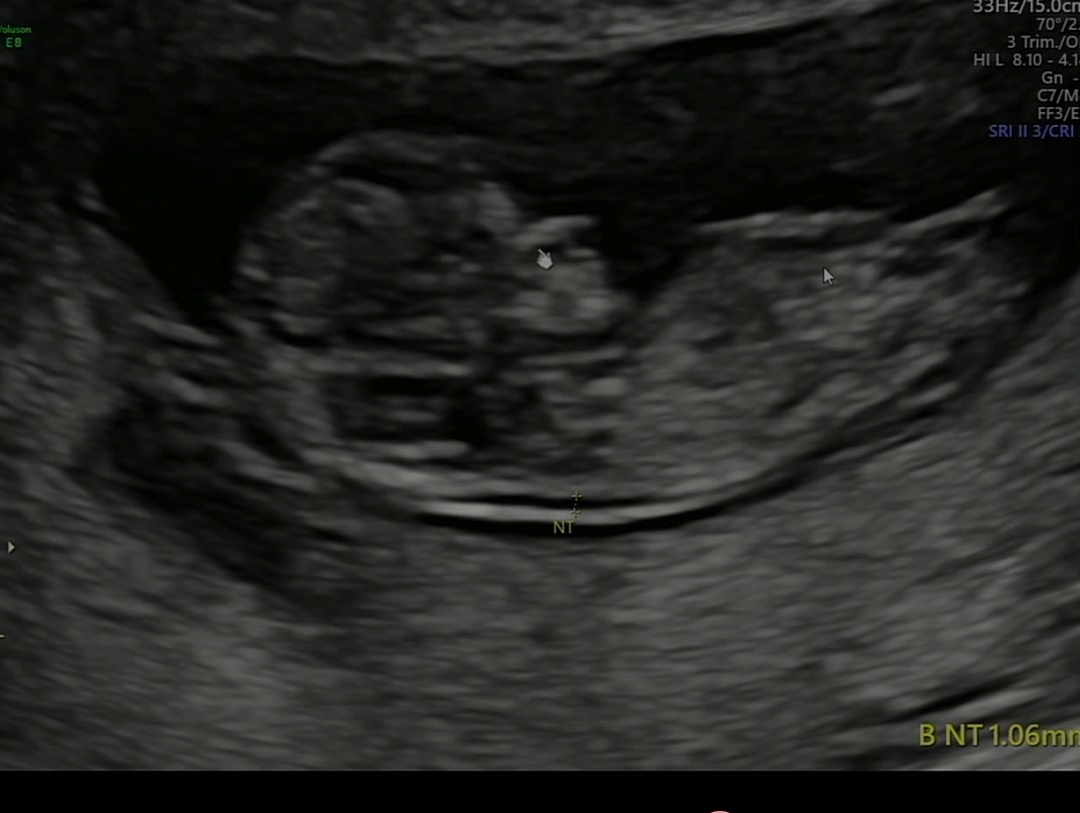

딸일까요? 아들일까요? 11주3일이에요!

각도법 부탁드립니다🙏🙏